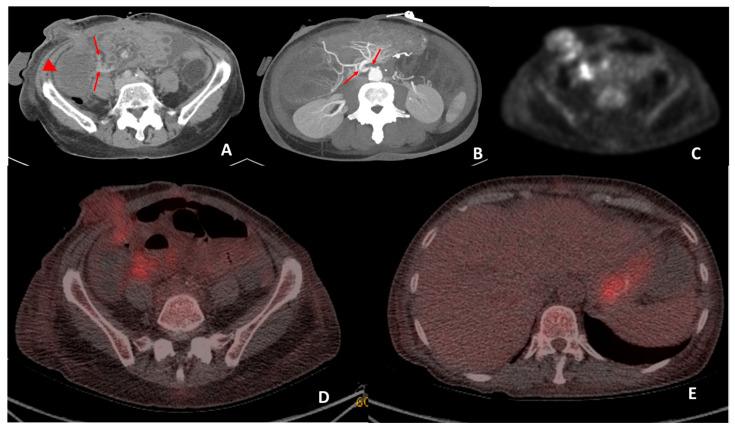

Multivisceral transplant (MVTx) refers to a composite graft from a cadaveric donor, which often includes the liver, the pancreaticoduodenal complex, and small intestine transplanted en bloc. It remains rare and is performed in specialist centres. Post-transplant complications are reported at a higher rate in multivisceral transplants because of the high levels of immunosuppression used to prevent rejection of the highly immunogenic intestine. In this study, we analyzed the clinical utility of 28 F-FDG PET/CT scans in 20 multivisceral transplant recipients in whom previous non-functional imaging was deemed clinically inconclusive. The results were compared with histopathological and clinical follow-up data. In our study, the accuracy of F-FDG PET/CT was determined as 66.7%, where a final diagnosis was confirmed clinically or via pathology. Of the 28 scans, 24 scans (85.7%) directly affected patient management, of which 9 were related to starting of new treatments and 6 resulted in an ongoing treatment or planned surgery being stopped. This study demonstrates that F-FDG PET/CT is a promising technique in identifying life-threatening pathologies in this complex group of patients. It would appear that F-FDG PET/CT has a good level of accuracy, including for those MVTx patients suffering from infection, post-transplant lymphoproliferative disease, and malignancy.

多脏器移植(MVTx)是指来自尸体供体的复合移植物,通常包括整块移植的肝脏、胰十二指肠复合体和小肠。这种移植仍然很少见,且在专科中心进行。由于用于预防高免疫原性肠道排斥反应的免疫抑制水平较高,多脏器移植术后并发症的报告发生率更高。在本研究中,我们分析了28例F-FDG PET/CT扫描在20例多脏器移植受者中的临床应用价值,这些受者之前的非功能性成像在临床上被认为无定论。将结果与组织病理学和临床随访数据进行比较。在我们的研究中,F-FDG PET/CT的准确性被确定为66.7%,最终诊断通过临床或病理学得到证实。在28次扫描中,24次扫描(85.7%)直接影响了患者的治疗管理,其中9次与开始新治疗有关,6次导致正在进行的治疗或计划中的手术停止。这项研究表明,F-FDG PET/CT在识别这类复杂患者群体中的危及生命的病变方面是一种有前景的技术。看来F-FDG PET/CT具有较高的准确性,包括对于那些患有感染、移植后淋巴细胞增生性疾病和恶性肿瘤的多脏器移植患者。